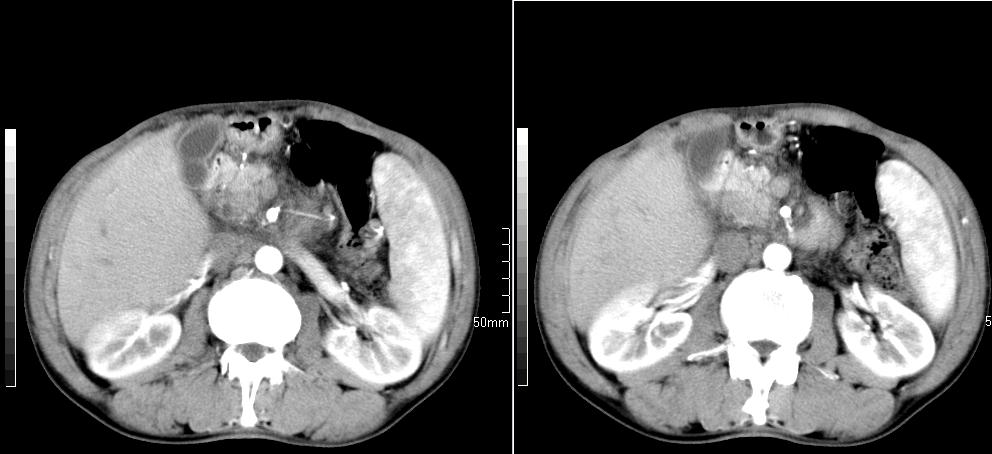

标题: CT26769:男,58岁,腹胀、腹部不适一年余 [打印本页]

标题: CT26769:男,58岁,腹胀、腹部不适一年余

胰头部是否正常。

1 慢性胰腺炎并假囊肿形成。2 慢性胆囊炎并累及肝边缘!

1)考虑慢性胰腺炎并假性囊肿形成。2) 慢性胆囊炎。3)肝内胆管扩张。

1肝内胆管扩张,性质待定,2慢性胰腺炎胰管扩张,胰腺颈部假囊肿,3肝左叶低密度为小囊肿,4胆囊炎。

1)考虑慢性胰腺炎并假性囊肿形成。2)肝内胆管稍扩张。